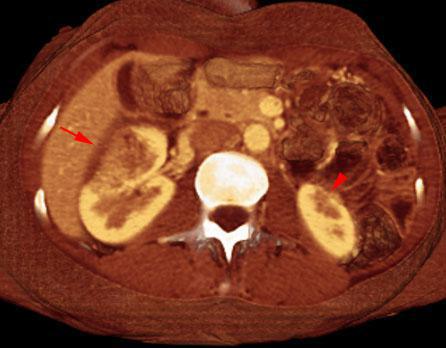

Pielonefritis bilateral aguda y crónica

VR seccional. Visión axial caudal. TC contrastado en fase venosa. Mujer de 39 años. Lesión hipodensa renal derecha con signos inflamatorios perirrenales (flecha). Atrofia cortical de origen pielonefrítico renal izquierda (punta de flecha)